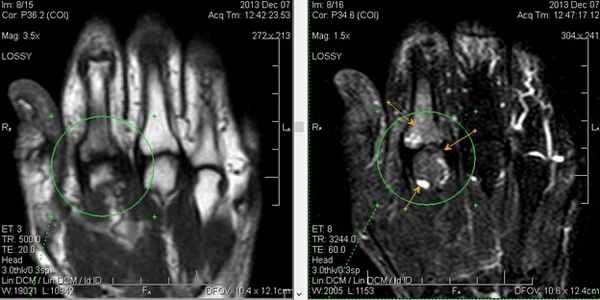

(Слева) Фронтальная Т2 ВИ с подавлением сигнала от жира: неоднородный отек костного мозга в полулунной кости без структурных изменений. Отрицательный локтелучевой индекс. Признаки не специфичны, следует иметь ввиду раннюю стадию развития остеонекроза.

(Справа) Рентгенография в ЗП проекции: многоочаговый остеонекроз вследствие применения стероидов. Полулунная кость имеет неоднородную плотность и коллапс проксимальной суставной поверхности. Проксимальный полюс ладьевидной кости уплощен. Однако остеонекроз ладьевидной кости является, как правило, посттравматическим, прием стероидов является фактором риска. (Слева) Рентгенография в ЗП проекции: несросшаяся линия перелома ладьевидной кости. Это, вероятное всего, истинное несращение, так как края перелома склерозированы, с субхондральной кистозной дегенерацией. Нет выраженного склероза проксимального полюса.

(Справа) Фронтальная Т1 МР-И, этот же случай: неоднородный низкий сигнал в проксимальном и дистальном отделах ладьевидной кости. Линия перелома видна нечетко. (Слева) Фронтальная T1FS постконтрастная МР-И: усиление дистального полюса, но низкий сигнал проксимального полюса, что указывает на отсутствие кровоснабжения. Несмотря на то, что здесь, вероятно, нежизнеспособные ткани, коллапса нет; оперативное лечение может иметь успех.

(Справа) Рентгенография запястья в ЗП проекции: у пациента с СКВ и остеонекрозом наблюдается коллапс проксимального полюса ладьевидной костив Определяется неровность суставной поверхности лучевого края полулунной кости и субхондральный перелом. При болезни Кинбека изменения со стороны лучевого края кости более характерны, чем со стороны локтевого края.